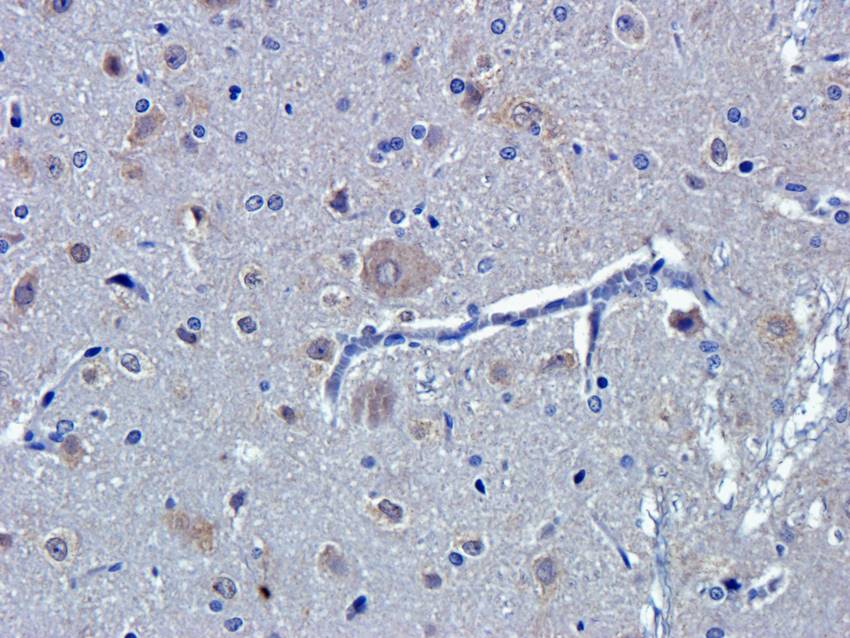

100 μg - PGP9.5 antibody [orb6713]Featured

ELISA, ICC, IF, IHC-P, WB

Human, Mouse, Rat

Rabbit

Polyclonal

Unconjugated

100 μg - FOXP3 antibody [orb34127]Featured